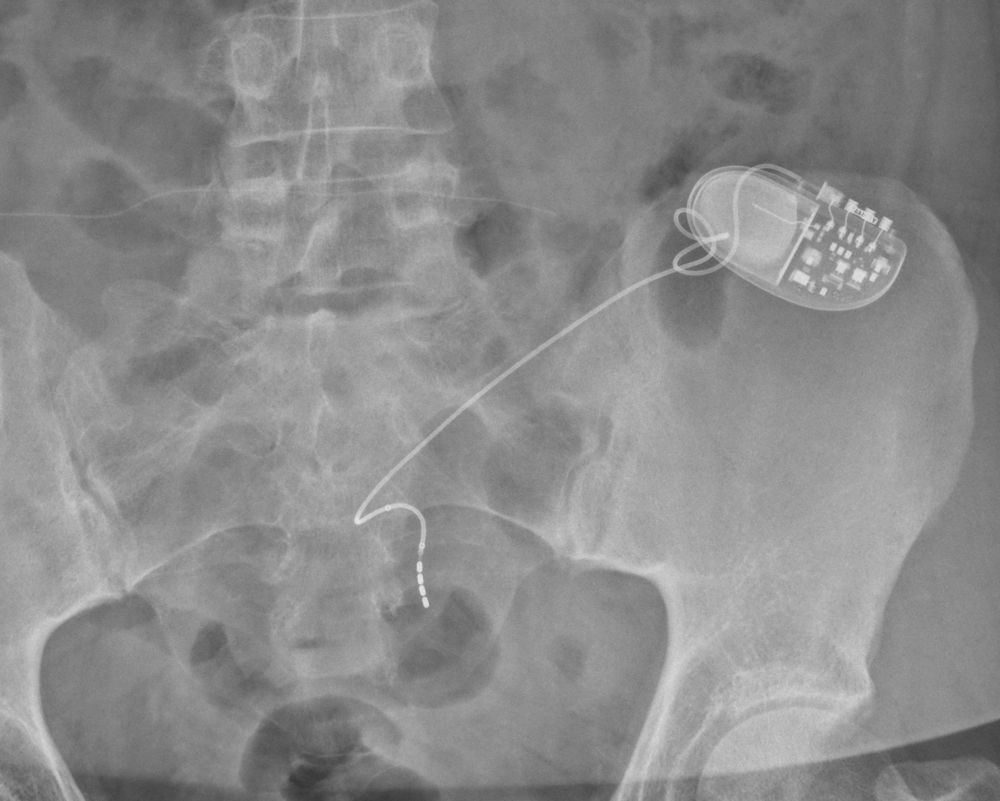

41856f9c-5cf5-44a9-b6d4-d396f0a7f263.png

X光片:一例植入的骶神经调控装置(右上方亮白色小盒)及导线位置示意。装置埋藏于臀部皮下,电极导线沿骶骨进入体内,尖端位于骶3神经孔处。通过发送轻柔电刺激,它如同“膀胱起搏器”般纠正膀胱神经信号的紊乱。